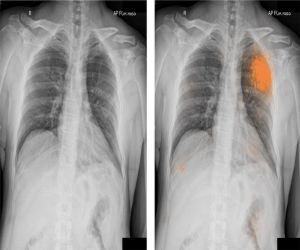

Radiografía de tórax.

- Corazón

- Los pulmones.

- Los vasos sanguíneos.

- Las vías respiratorias.

- Los huesos del tórax y de la columna vertebral.